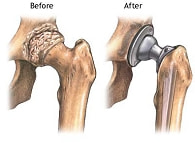

人工関節置換術

また、耐用年数も飛躍的に伸びています。しかし、ひじや手の手術成績はまだそれほどよくありません。どちらかというと、体重を支える大きな関節のほうが手術に適しているようです。